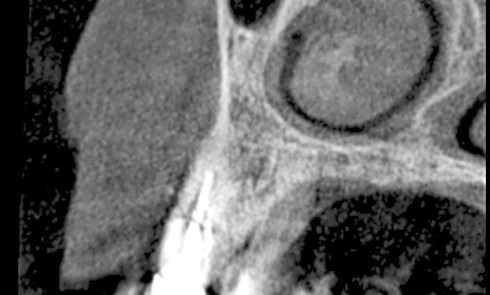

Article réservé à nos abonnés Discussion autour d’un cas complexe d’inclusions multiples atypiques